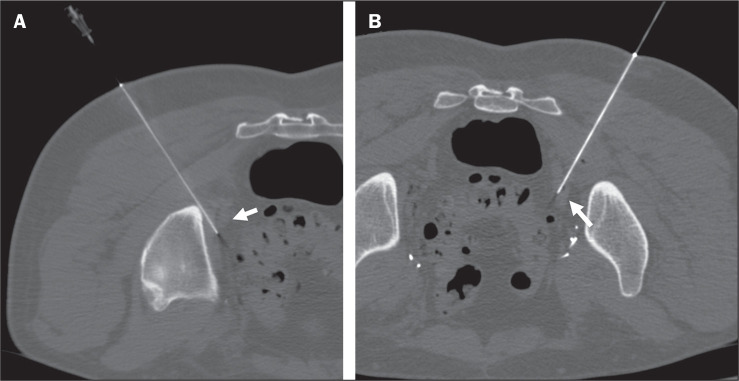

Computed tomography-guided preoperative charcoal tattooing in patients with recurrent prostate cancer after prostatectomy and undergoing pelvic salvage lymphadenectomy.

Abstract Image